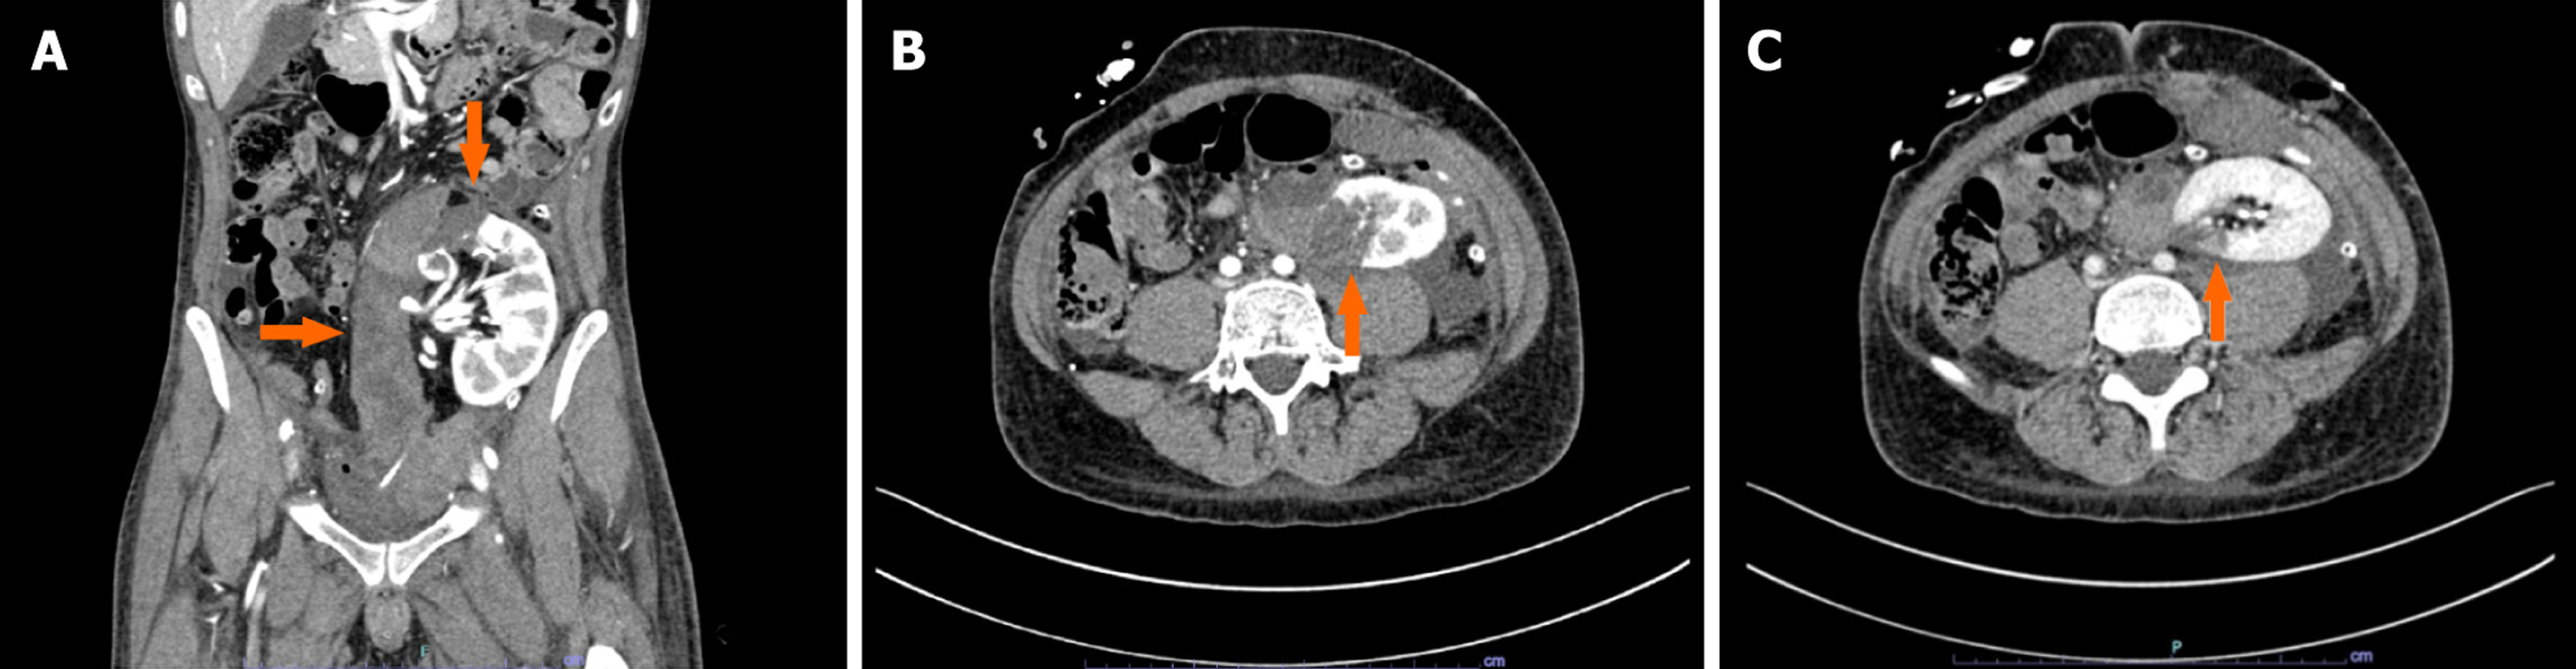

After a brief bedside assessment with a Doppler ultrasound (US) scan (showing a well-perfused graft surrounded by a large retro-peritoneal fluid collection), the recipient underwent immediate contrast-enhanced computed tomography (CT) evaluation. The imaging study demonstrated a large (9.6 cm × 4.3 cm × 17 cm), retro-peritoneal hematoma (Figure 1A) with features of active bleeding from the upper pole of the transplanted kidney (Figure 1B). A focal laceration of the renal cortex not involving the calyceal system and a 3.8-cm-wide area of parenchymal hypoperfusion were noticed in proximity to the blushing spot (Figure 1C). Therefore, a plan was made for surgical exploration.